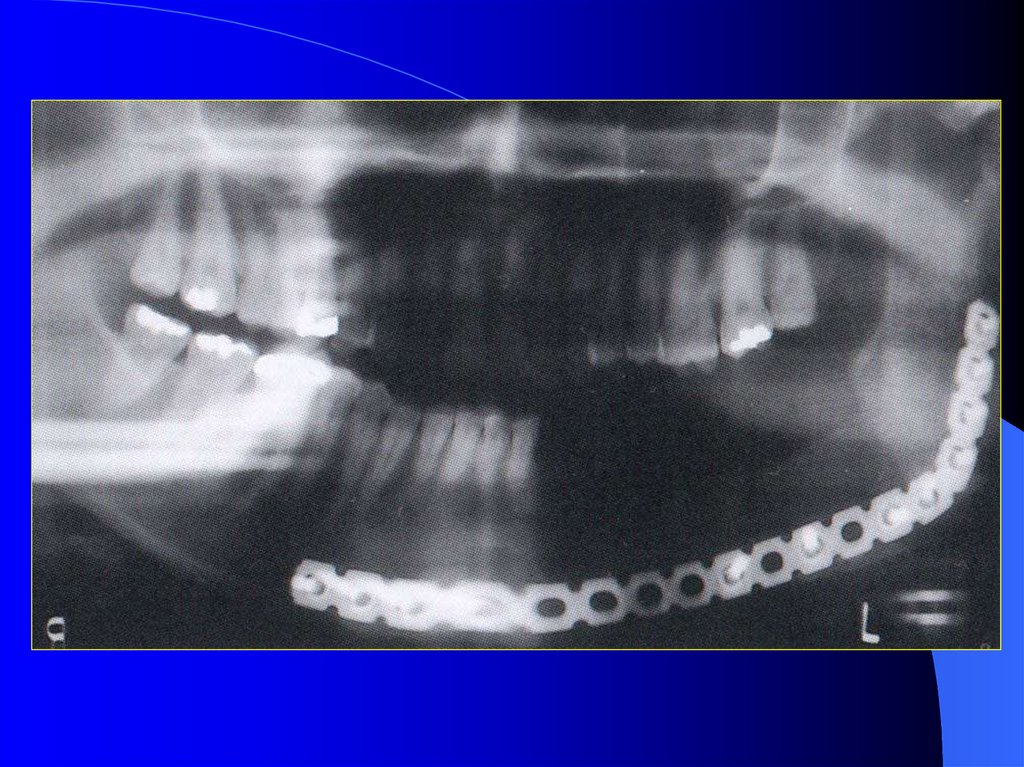

32. Devamlılığın bozulduğu durumlarda oklüzyonun sağlanması:

1- El kontrolü ile yapılan egzersizlerle

kapanış ilişkisinin sağlanması

2-Rehber düzlemler hazırlanması

3-Azılar bölgesinde çift sıra diş dizimi

4-Azılar bölgesinde palatinalde rehber

akrilik düzlemler hazırlanması